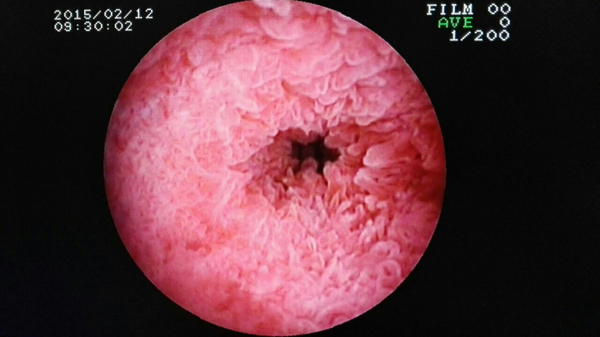

手术过程中

2015年1月27日,韦女士如约来到肝胆外科,这一次,肝胆外科多名医生专门为她取肝内胆管结石。1月29日第一次、2月2日第二次、2月3日第三次……一直到2月11日,持续两周时间,共取九次,韦女士的肝内胆管结石总算是全部清除完了。